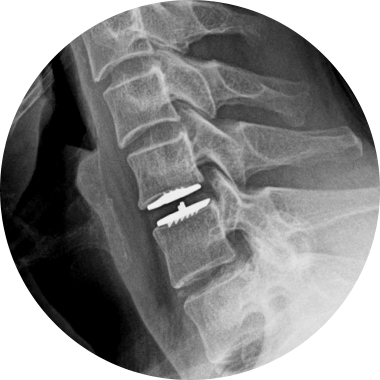

손상된 경추 디스크를 제거한 후, 척추체 사이에 인공디스크를 삽입하는 수술적 치료입니다.

손상된 경추 디스크를 모두 제거하고 빈 공간으로 인공디스크를 삽입하여 본래의 디스크처럼 정상적인 기능을 하도록 합니다.

STEP 01

손상된 디스크

STEP 02

손상된 디스크 제거

STEP 03

인공디스크 삽입

경추 인공디스크 치환술 후 자유로운 목 움직임